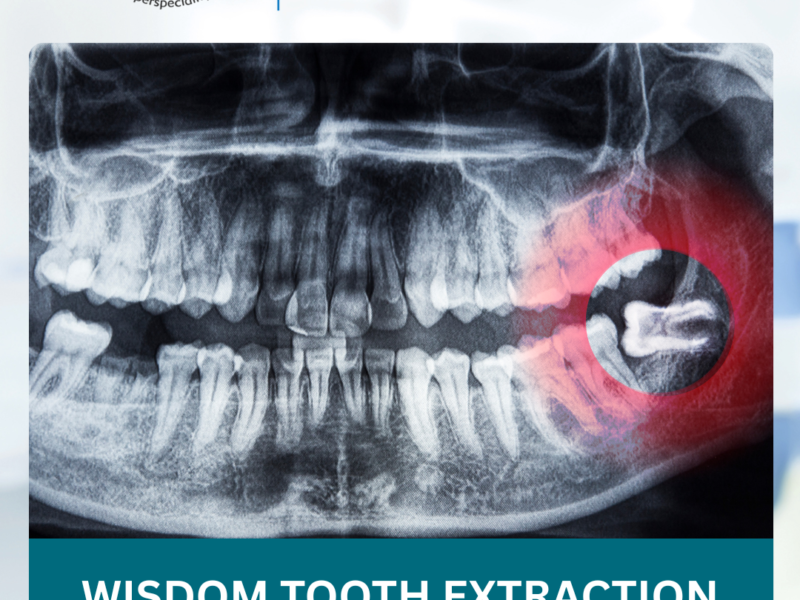

1. Consultation & X-Rays

Your dentist will examine your teeth and take X-rays to assess positioning and recommend removal if necessary.